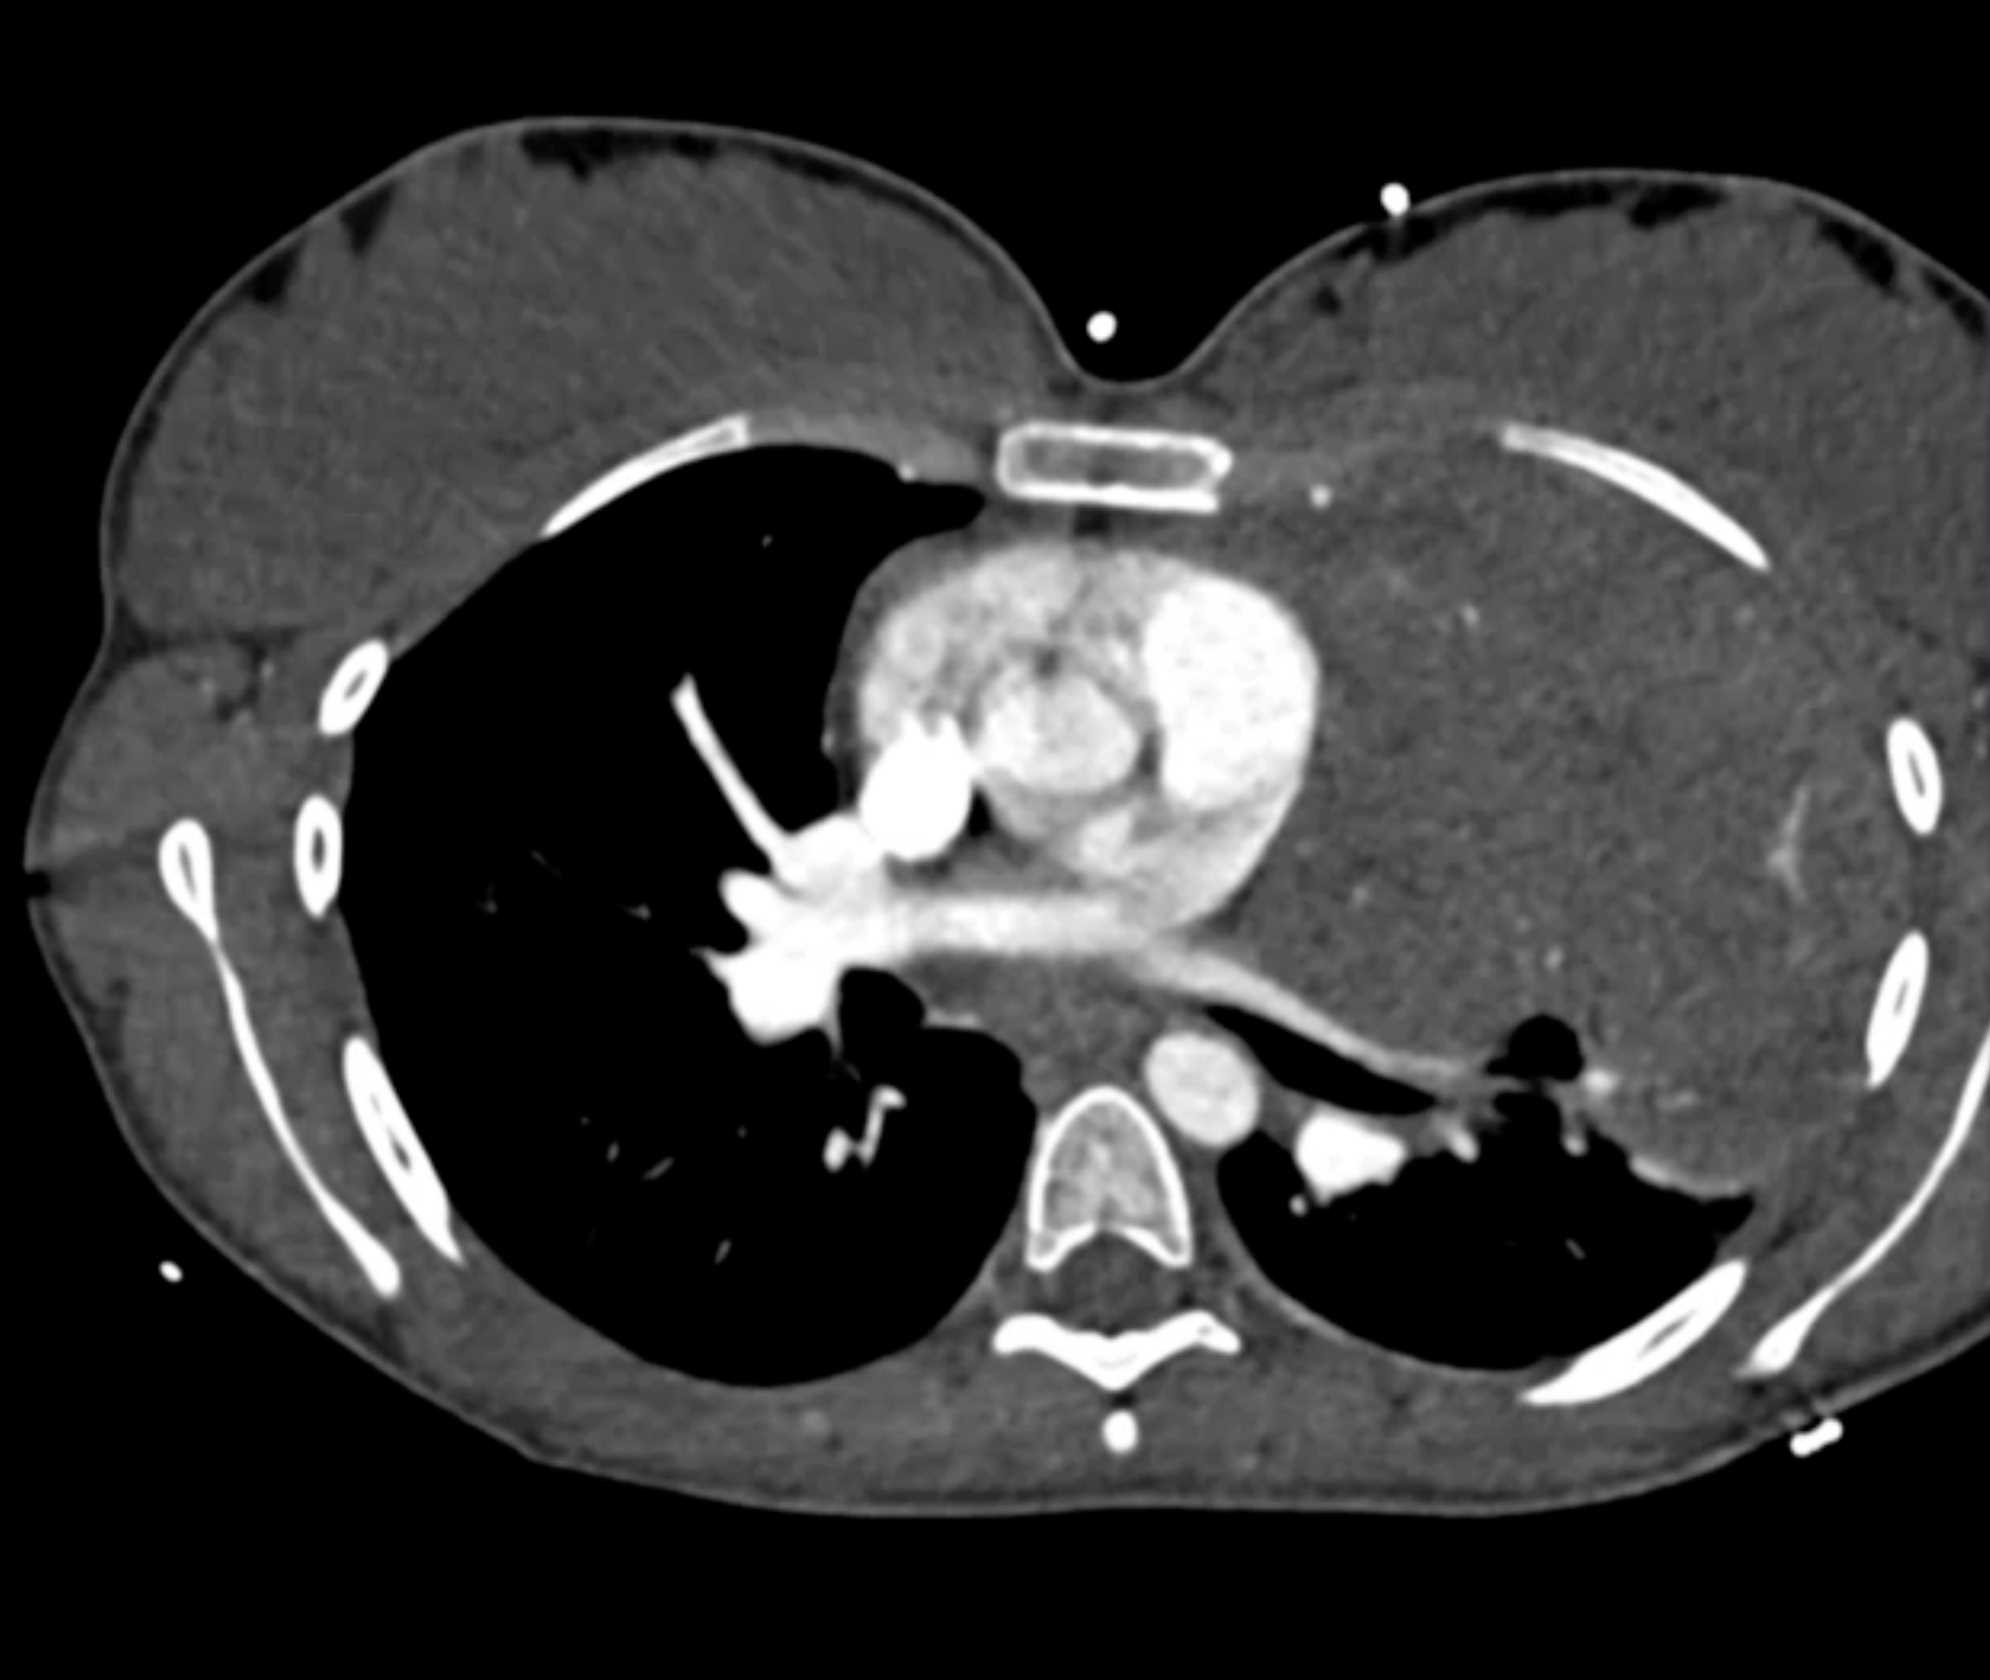

Subtle Adenocarcinoma Pancreas